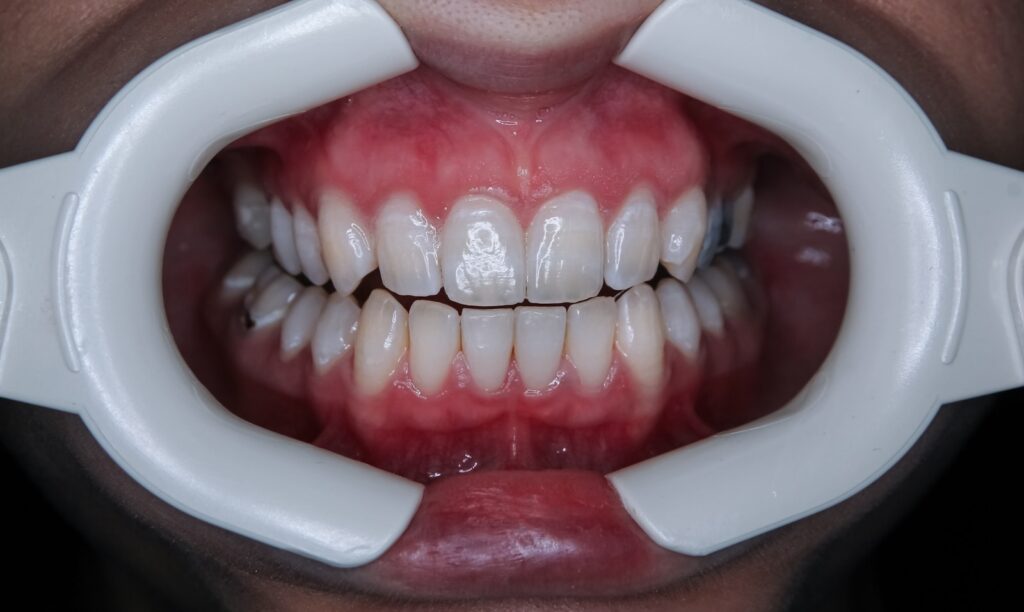

Most people understand that poor dental hygiene leads to cavities and gum disease, but groundbreaking research reveals a far more serious consequence: it could be silently threatening your heart. A remarkable 17-year study following older adults found that those with periodontitis faced a 50% higher risk of developing ischemic heart disease, with women showing an even more alarming 110% increased risk. Even more striking, recent research shows that seniors with no remaining teeth have an 83% higher risk of dying from cardiovascular disease compared to those who’ve maintained at least 20 teeth. This isn’t just about statistics—it’s about a hidden health crisis affecting millions of older adults. As we age, the stakes of dental neglect become literally a matter of life and death. The mouth, once thought to be separate from the rest of the body, is now recognized as a gateway that can either protect or endanger our cardiovascular system.